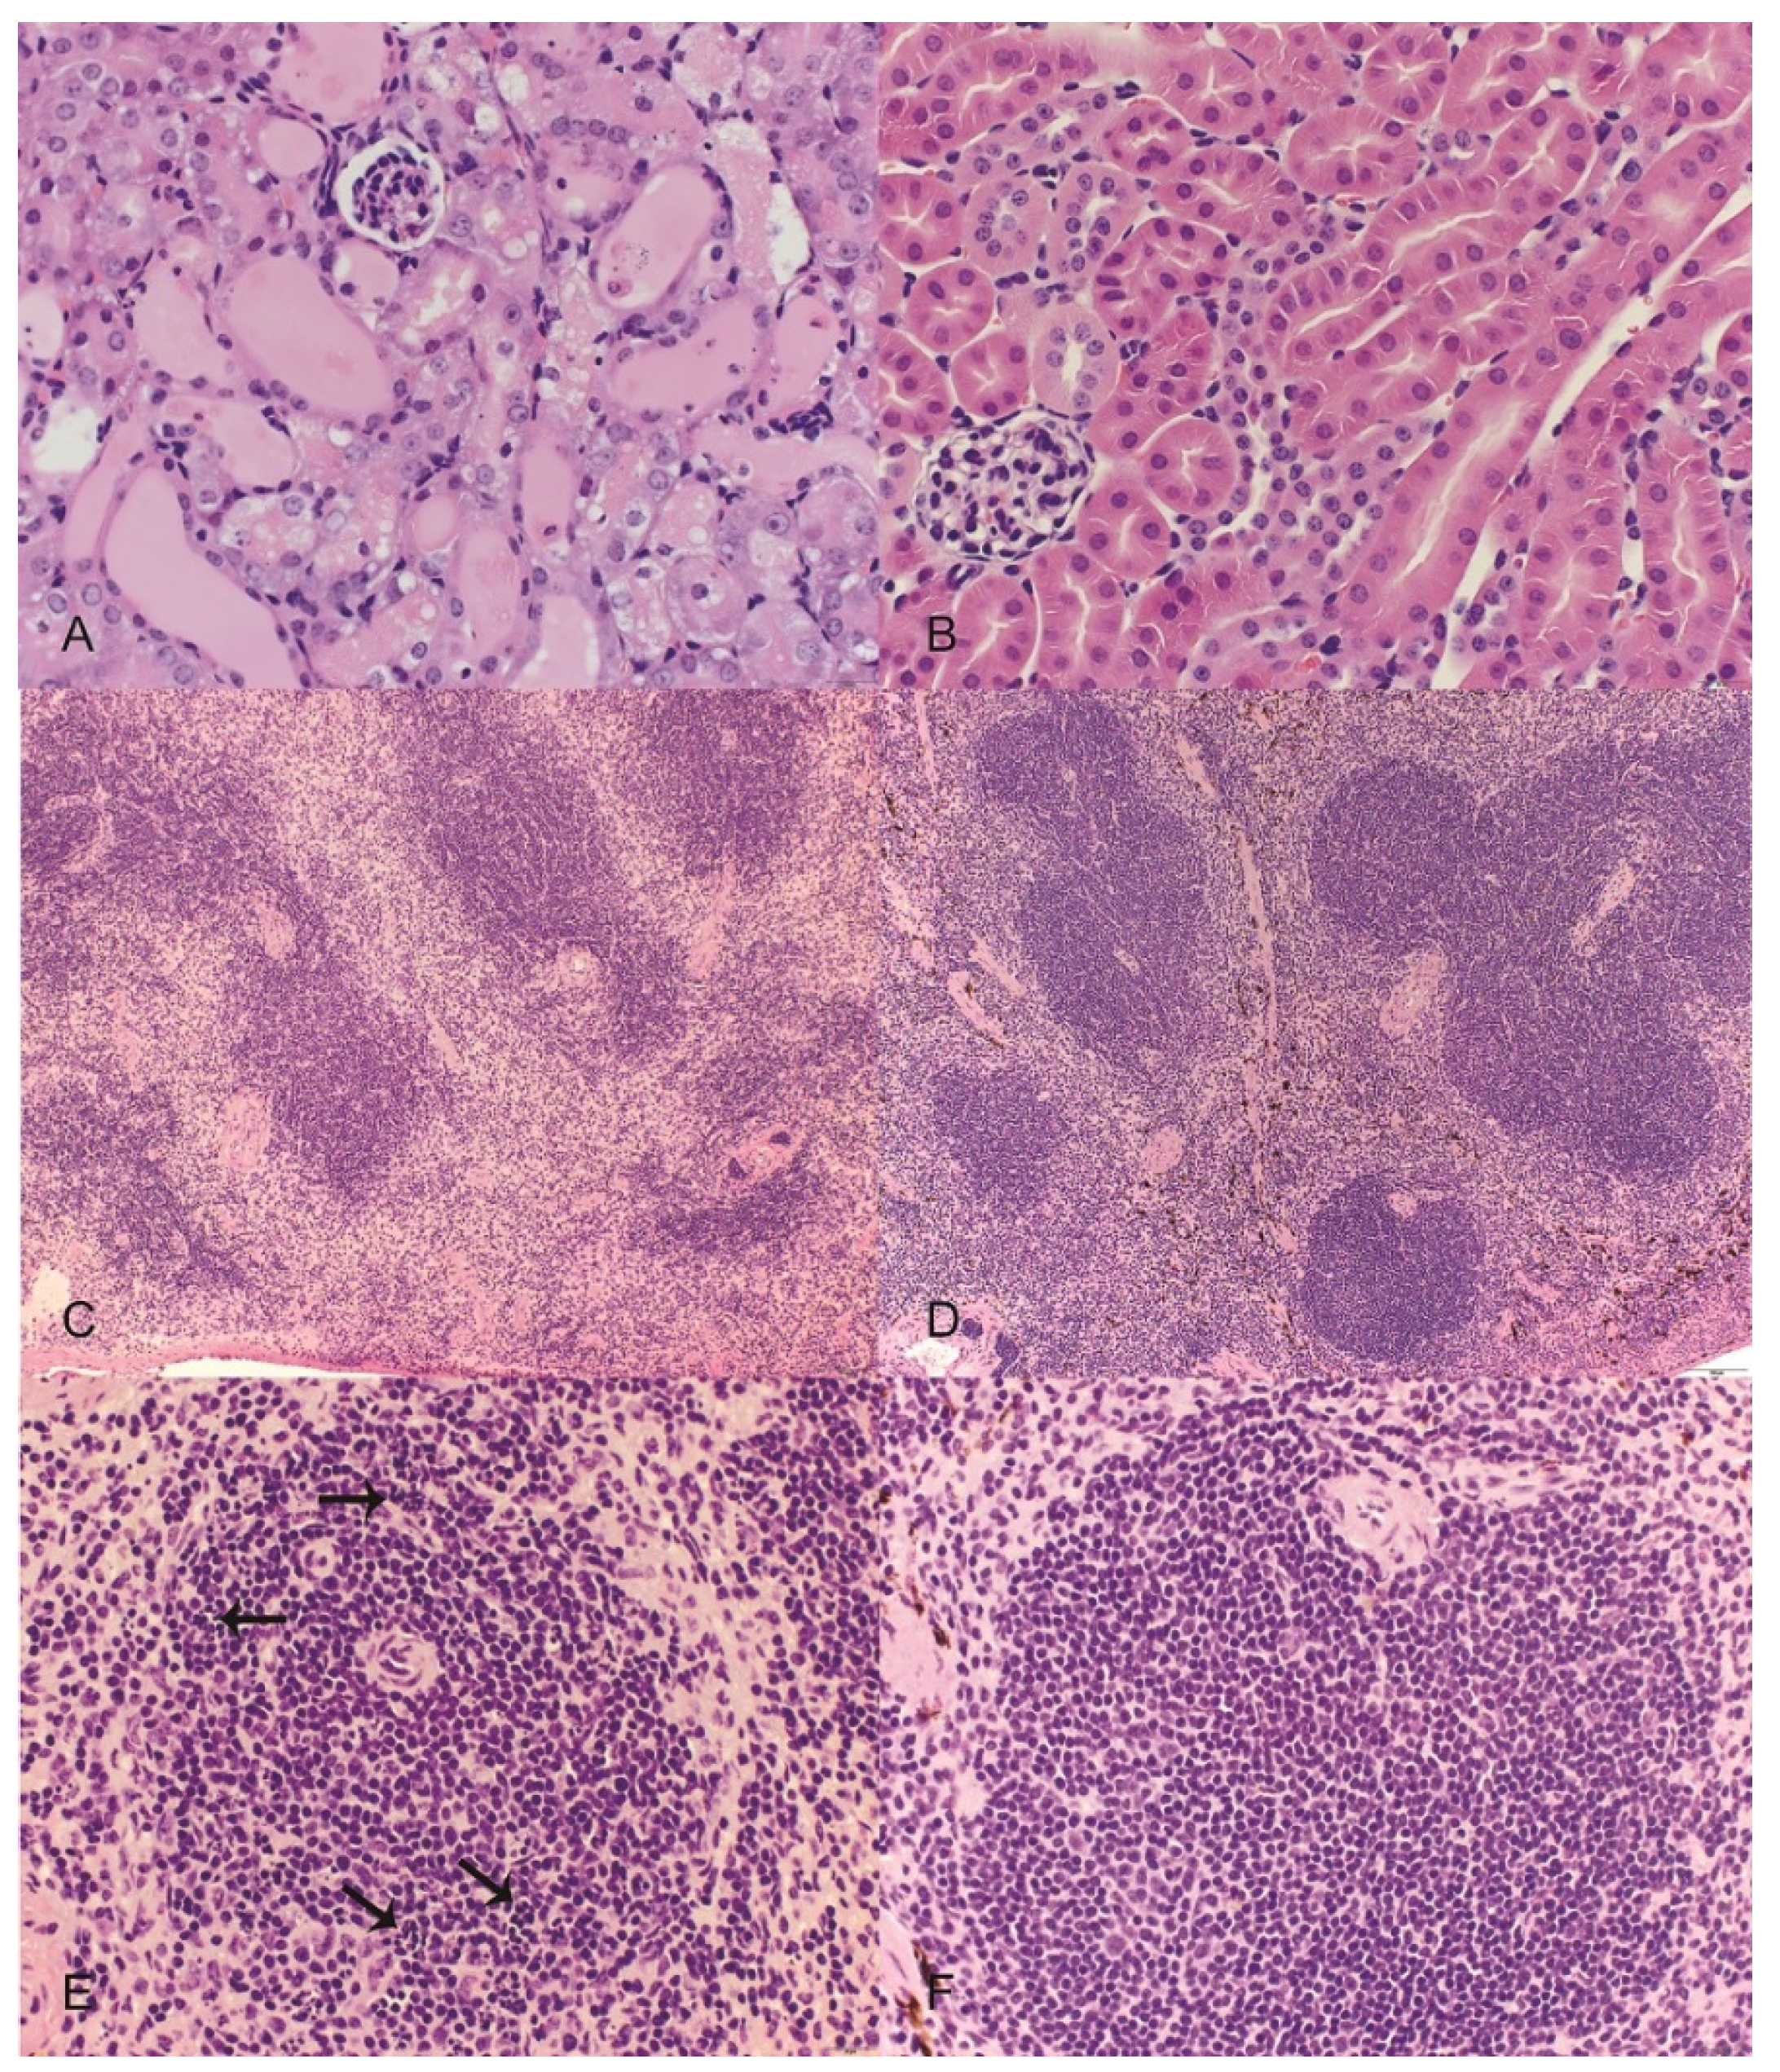

Significant lesions were observed in the renal cortex of all examined OR treated mice and included variable degeneration and necrosis of the tubular epithelium with regeneration, tubular ectasia, and tubular proteinosis (Figure 3A). Affected tubules often contained low numbers of sloughed epithelial cells. The renal tubules of control mice were unremarkable (Figure 3B). The spleens of OR treated mice were smaller with reduced overall cellularity relative to control mice (Figure 3C,D) and the white pulp of OR treated mice was characterized by moderate to high numbers (10%–50%) of pyknotic and karyorrhectic lymphocytes (Figure 3E,F). Moderate random hepatocellular vacuolation was observed in one OR-treated mouse (Figure 4). Lesions were also observed in the stomachs of mice given OR and included presence of neutrophils within the lamina propria of the non-glandular stomach with variable associated thickening of the squamous epithelium and submucosal edema; however, low numbers of neutrophils were also occasionally observed in the lamina propria of control mice at the junction of the glandular and non-glandular stomach.

Figure 3. Representative images from mice treated with orellanine (OR) or saline controls (CON). Hematoxylin and eosin. (A) (top left) Kidney from an OR-treated mouse revealing variable tubular degeneration and ectasia with luminal accumulations of proteinic fluid and occasional sloughed cells; (B) (top right) kidney from a CON mouse with normal tubular morphology; (C) (middle left) spleen from an OR-treated mouse revealing an overall reduction in red and white pulp cellularity; (D) (middle right) spleen from a CON mouse with normal cellularity and well-defined red and white pulp margins; (E) (bottom left) higher magnification of white pulp from an OR-treated mouse revealing numerous pyknotic and karyorrhectic lymphocytes (arrows); (F) (bottom right) higher magnification of white pulp from a CON mouse with normal morphology. Scales: A,B,E,F = 600× magnification; C,D = 100× magnification.